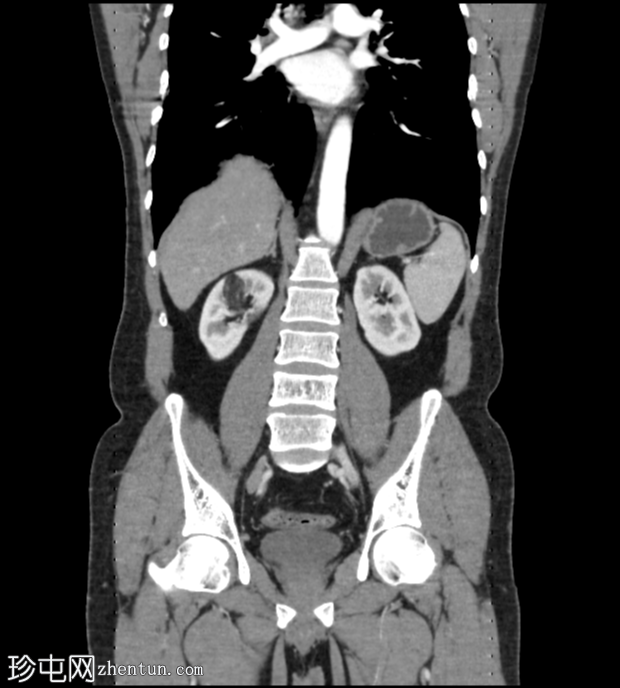

冠状位增强扫描(门静脉期)

CT扫描显示右肾上半部可见一部分边界清晰的肿块,其密度成分包含软组织和脂肪。

其余腹腔脏器未见明显异常。

可见累及L4椎体的血管瘤。

目前的CT

影像

学表现为右侧肾血管平滑肌脂肪瘤,无内部出血。